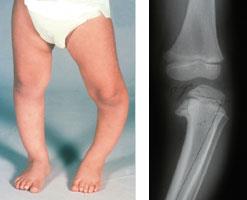

Photo and x-ray of child with Blount's disease

(Left) Toddler with infantile Blount's disease involving the left leg. (Right) X-ray of the left knee shows the Blount's abnormality along the top of the shinbone.

Courtesy of Texas Scottish Rite Hospital for Children

In a child under the age of 2 years, it may be impossible to distinguish infantile Blount's disease from physiologic genu varum. By the age of 3 years, however, the bowing will worsen in a patient with Blount's disease, and an obvious problem can often be seen on an X-ray.